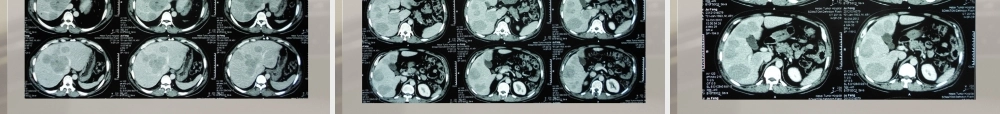

介入病房典型病例放射科杨东强肝血管瘤的介入病例病例特点①患者中年男性。②于当地体检诊为肝血管瘤。③患者2012-10-12于当地饶阳县医院体检,腹部超声示:肝内多发低回声团,考虑血管瘤可能性大。无腹痛腹胀,无皮肤黄染,无恶心呕吐,无胸闷气短。为求介入治疗,就诊于我院,门诊以“肝血管瘤”收入院。④查体:肝脏下缘位于右锁骨中线上距肋下缘3cm,剑突下4cm,质韧,边缘钝。初步诊断及诊断依据初步诊断为肝血管瘤。诊断依据为:①患者中年男性。②于当地体检诊为肝血管瘤③查体:肝脏下缘位于右锁骨中线上距肋下缘3cm,剑突下4cm,质韧,边缘钝。④上腹部增强CT(2012-10-17,我院)示:肝内多发血管瘤。上腹增强CT图像上腹增强CT-动脉期上腹增强CT-门脉期其他断层鉴别诊断(1)原发性肝癌:起病隐匿,早起缺乏典型症状。临床症状显著者,病情大多已进入中、晚期。常在肝硬化的基础上发生,或者以转移病灶为首先表现。主要症状为肝区疼痛,肝脏呈进行性增大,质地坚硬,会出现梗阻性黄疸及肝硬化的征象。甲胎蛋白多大于1210,而肝血管瘤甲胎蛋白在正常范围内。(2)肝脓肿:一般多有发热,肿大的肝表面平滑无结节,触痛明显,白细胞计数升高,CT表现为无明显强化。鉴别诊断(3)肝转移瘤:原发于胃肠道、呼吸道、泌尿生殖道、乳房等处的癌灶常转移至肝,这类继发型肝癌主要与原发性肝癌相鉴别,病情发展较缓慢,症状较轻,AFP检测除少数原发癌在消化道的病例可阳性外,一般为阴性,常为多发。(4)肝囊肿、肝腺瘤及局灶性结节增生:患者多无临床症状,常为查体发现,CT表现不支持基本排除,有时需穿刺取病理才能确定。手术记录患者在局部麻醉下行腹腔干、肝中动脉、肝右动脉、肝左动脉造影术;肝中动脉、肝右动脉、肝左动脉灌注化疗栓塞术。术中造影示:实质期肝脏左、右叶可见雪片状染色,“树上挂果征”阳性,未见肝动脉-门静脉瘘,经导管注入博来霉素15mg与碘油25ml的混合乳化物,行灌注化疗栓塞后,复查肝动脉造影肿瘤染色大部分消失。腹腔干造影肝右动脉的造影肝右、肝中动脉的栓塞后造影肝左动脉的造影最后复查造影肝转移瘤的介入病例病例特点①患者中年男性。②肝区疼痛诊为直肠癌肝转移1年余。③患者于2010年12月初无明显诱因出现肝区疼痛,后就诊于唐河县医院行肝脏彩超示:肝内多发实性占位,癌的可能性大。于2010年12月17日就诊于我院外二科,结肠镜示:结肠息肉,直肠病变;病理示:灶性腺体异型增生,不除外类癌;北京协和医院会诊我院...